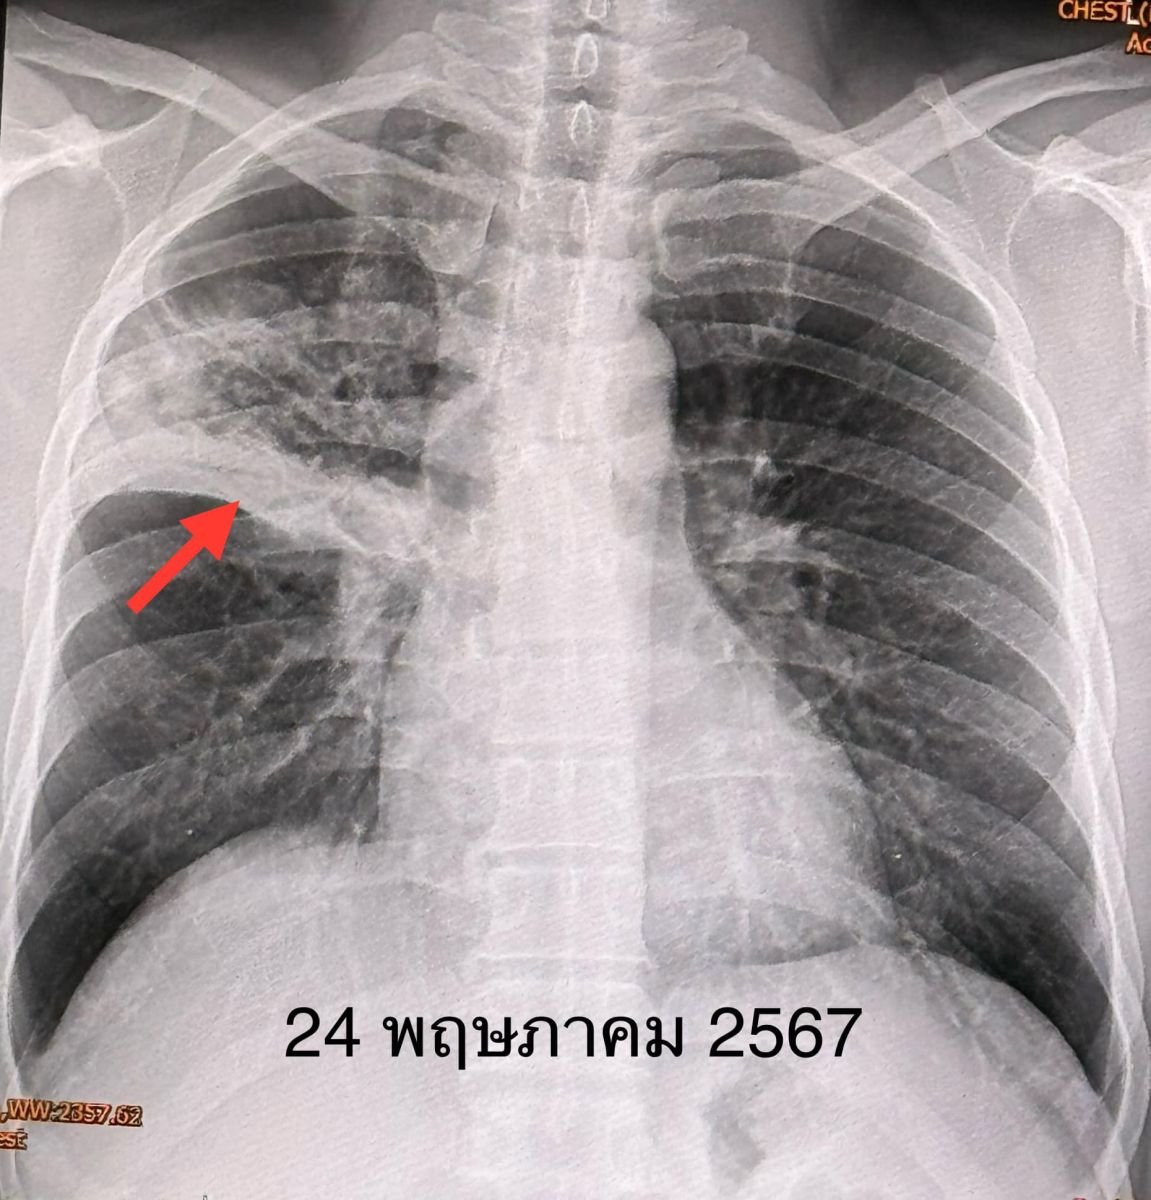

แพทย์วินิจฉัย ว่าเป็นวัณโรคปอด เริ่มยารักษาวัณโรค 4 ขนานคือ INH, rifampicin, pyrazinamide, ethambutol และวิตามิน B6 ผู้ป่วยกินยาได้ ไม่แพ้ยา หลังกินยาไข้ลง ไม่ไอ ไม่มีเสมหะ ผลเพาะเชื้อวัณโรค 1 เดือนต่อมา ขึ้นเชื้อวัณโรค M.tuberculosis ไวต่อยารักษาวัณโรคทุกตัว เอกซเรย์ปอดหลังได้รับยา 5 สัปดาห์ ฝ้าขาวที่ปอดข้างขวาด้านบนดีขึ้น ต้องให้ยารักษาวัณโรค 4 ขนานต่อไปจนครบ 2 เดือน แล้วลดยาเหลือ INH, rifampicin และวิตามิน B6 รับประทานต่อไปจนครบ 6 เดือน